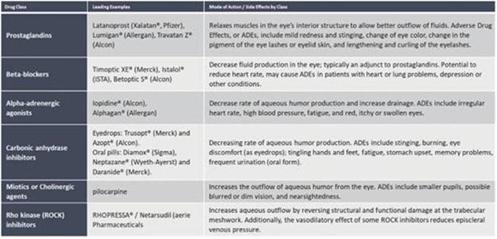

| ● | INM-088 being a once-a-day or twice-a-day eye drop medication that will compete with treatment modalities in the medicines category; |

CBN is also the active ingredient in our second drug candidate, INM-088, which is in preclinical studies as a potential treatment for glaucoma. We are conducting studies to test INM-088’s ability to provide neuroprotection and reduce intraocular pressure in the eye. We compared several cannabinoids, including CBD and THC, to determine which cannabinoid was the best drug candidate for the treatment of glaucoma. Of all the cannabinoids examined in preclinical studies, CBN demonstrated the most optimal neuroprotection effect. Furthermore, CBN also exhibited intraocular pressure reduction capability. INM-088 is in advanced formulation development.

Current treatments for glaucoma primarily focus on decreasing fluid build-up in the eye. Our data has shown that INM-088 may provide neuroprotection in addition to modulating intraocular pressure by improving drainage of fluid in the eye. Thus far, we have conducted numerous preclinical pharmacology studies to demonstrate these effects.